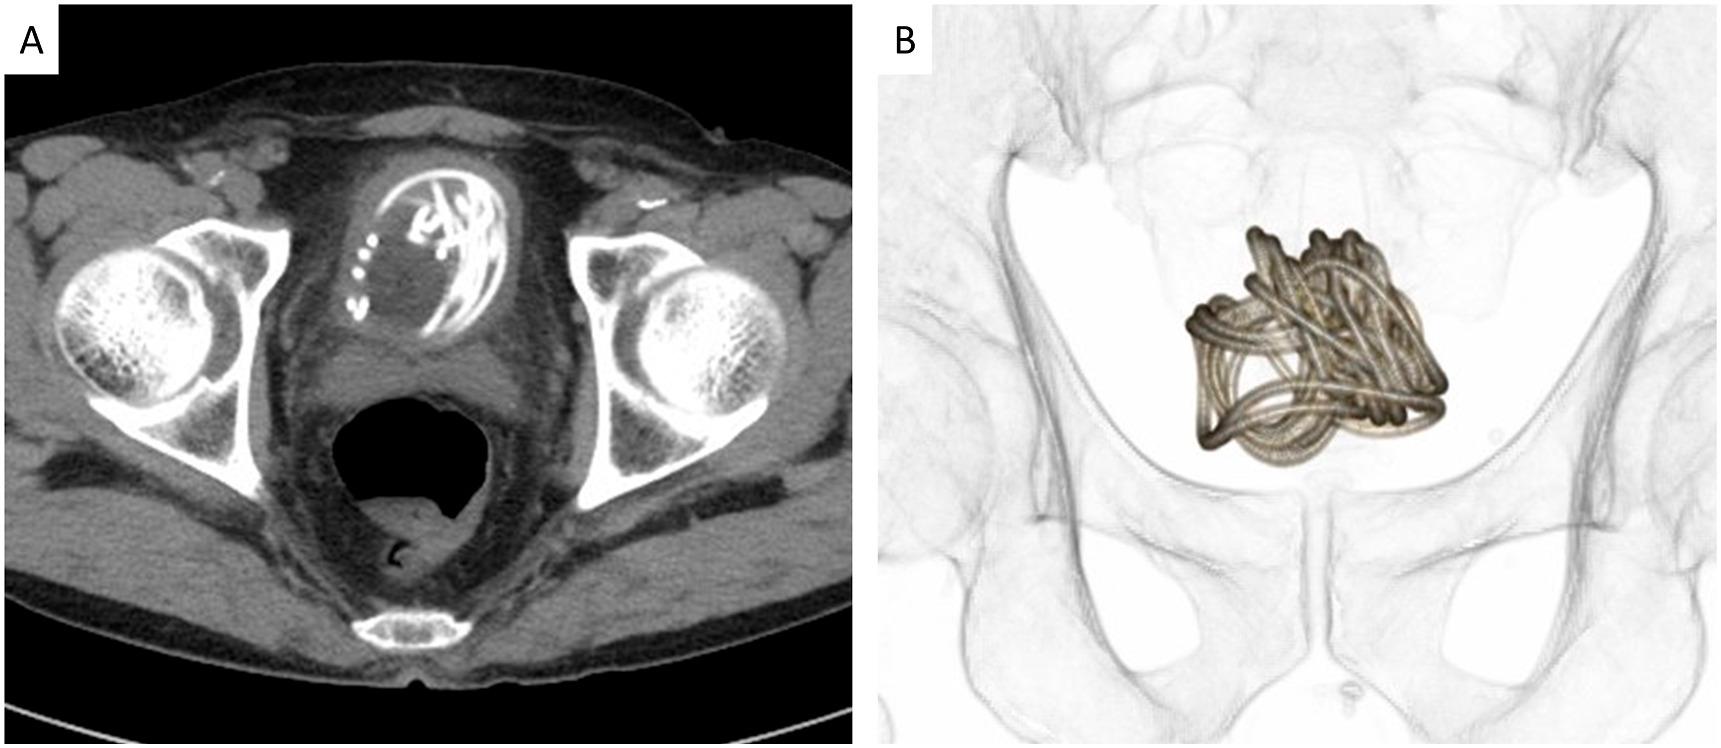

膠製跳繩在老翁膀胱裡纏成一團。(互聯網)

匪夷所思……日本櫪木縣一名79歲老翁因排尿困難、小便時有灼熱感且常覺疼痛,到當地一間大學醫院求醫,醫生替他做X光檢查,赫然發現他膀胱裡竟有一條長長的纏繞物。

詢問後,老翁才透露自己將一條膠製跳繩插入尿道,因跳繩沒有手柄,過程太順暢,所以整條可沒入膀胱裡,但老翁並沒解釋為甚麼要這樣做。

該條跳繩長約2.3米,在老翁膀胱裡已打結纏繞成球狀,醫生無法沿原先進入的路徑取出,最後只好做內窺鏡微創手術,在老翁腹部割開一個小切口將跳繩取出。老翁於手術後並無大礙,也沒出現併發症。